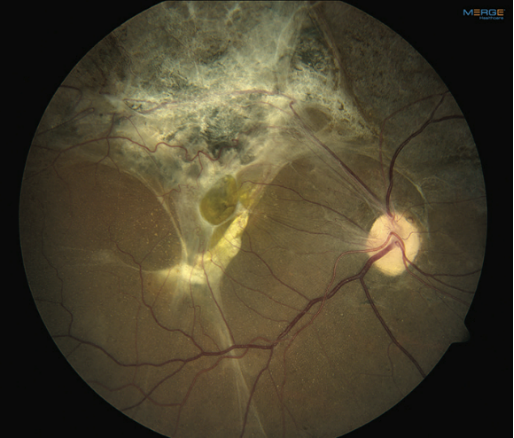

7.视网膜激光:在切开的视网膜边缘打两到三排激光(见图1)。

图1. 在切开的视网膜边缘打两到三排激光

患者为24岁男性,3个月前头部及眼眶多处枪伤,左眼视力无光感,视网膜完全脱离,与晶状体后囊粘连,无法手术;右眼视力20/150。眼前节检查正常;散瞳后检查眼底显示后极部广泛瘢痕,可见视网膜前膜和视网膜下膜(见图2);OCT提示黄斑区视网膜脱离(见图3)。

图2. 左眼后极部广泛瘢痕,可见视网膜前膜和视网膜下膜,与巩膜损伤一致